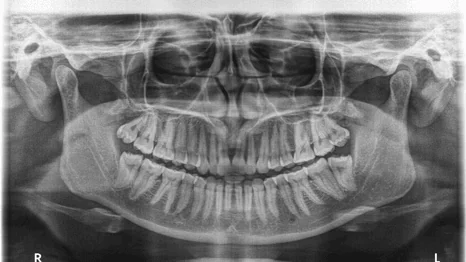

On intraoral and radiographic examination, there was no cause of pain to be actually originating from the premolar region .

Figure 1 Panoramic imaging showing no evidence of odontogenic involvement for pain site